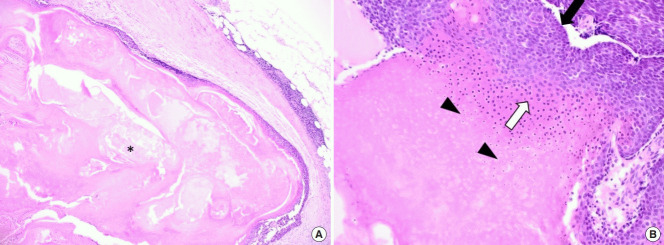

毛母质瘤是一种良性皮肤肿瘤,起源于分化为毛母质细胞的表皮原始基底细胞。 大多数毛母质瘤的直径约为 1 厘米,而直径为 5 厘米或以上的则被归类为巨大毛母质瘤。 头颈部毛母质瘤的鉴别诊断包括皮脂腺囊肿、骨化性血肿、鳃残余、耳前窦、淋巴结肿大、巨细胞瘤、软骨瘤、皮样囊肿、退化性纤维黄瘤、异物反应、皮肤骨瘤。 准确诊断毛母质瘤需要放射影像学和组织病理学检查。 其组织病理学特征包括外围的细胞簇(包括有核基底样细胞)和中心的无核影细胞(也称为“鬼细胞”)呈圆形排列。 巨大的毛母质瘤通常与外伤有关,并且有时会在外伤事件后观察到溃疡或坏死组织物质的局灶性经表皮消除。